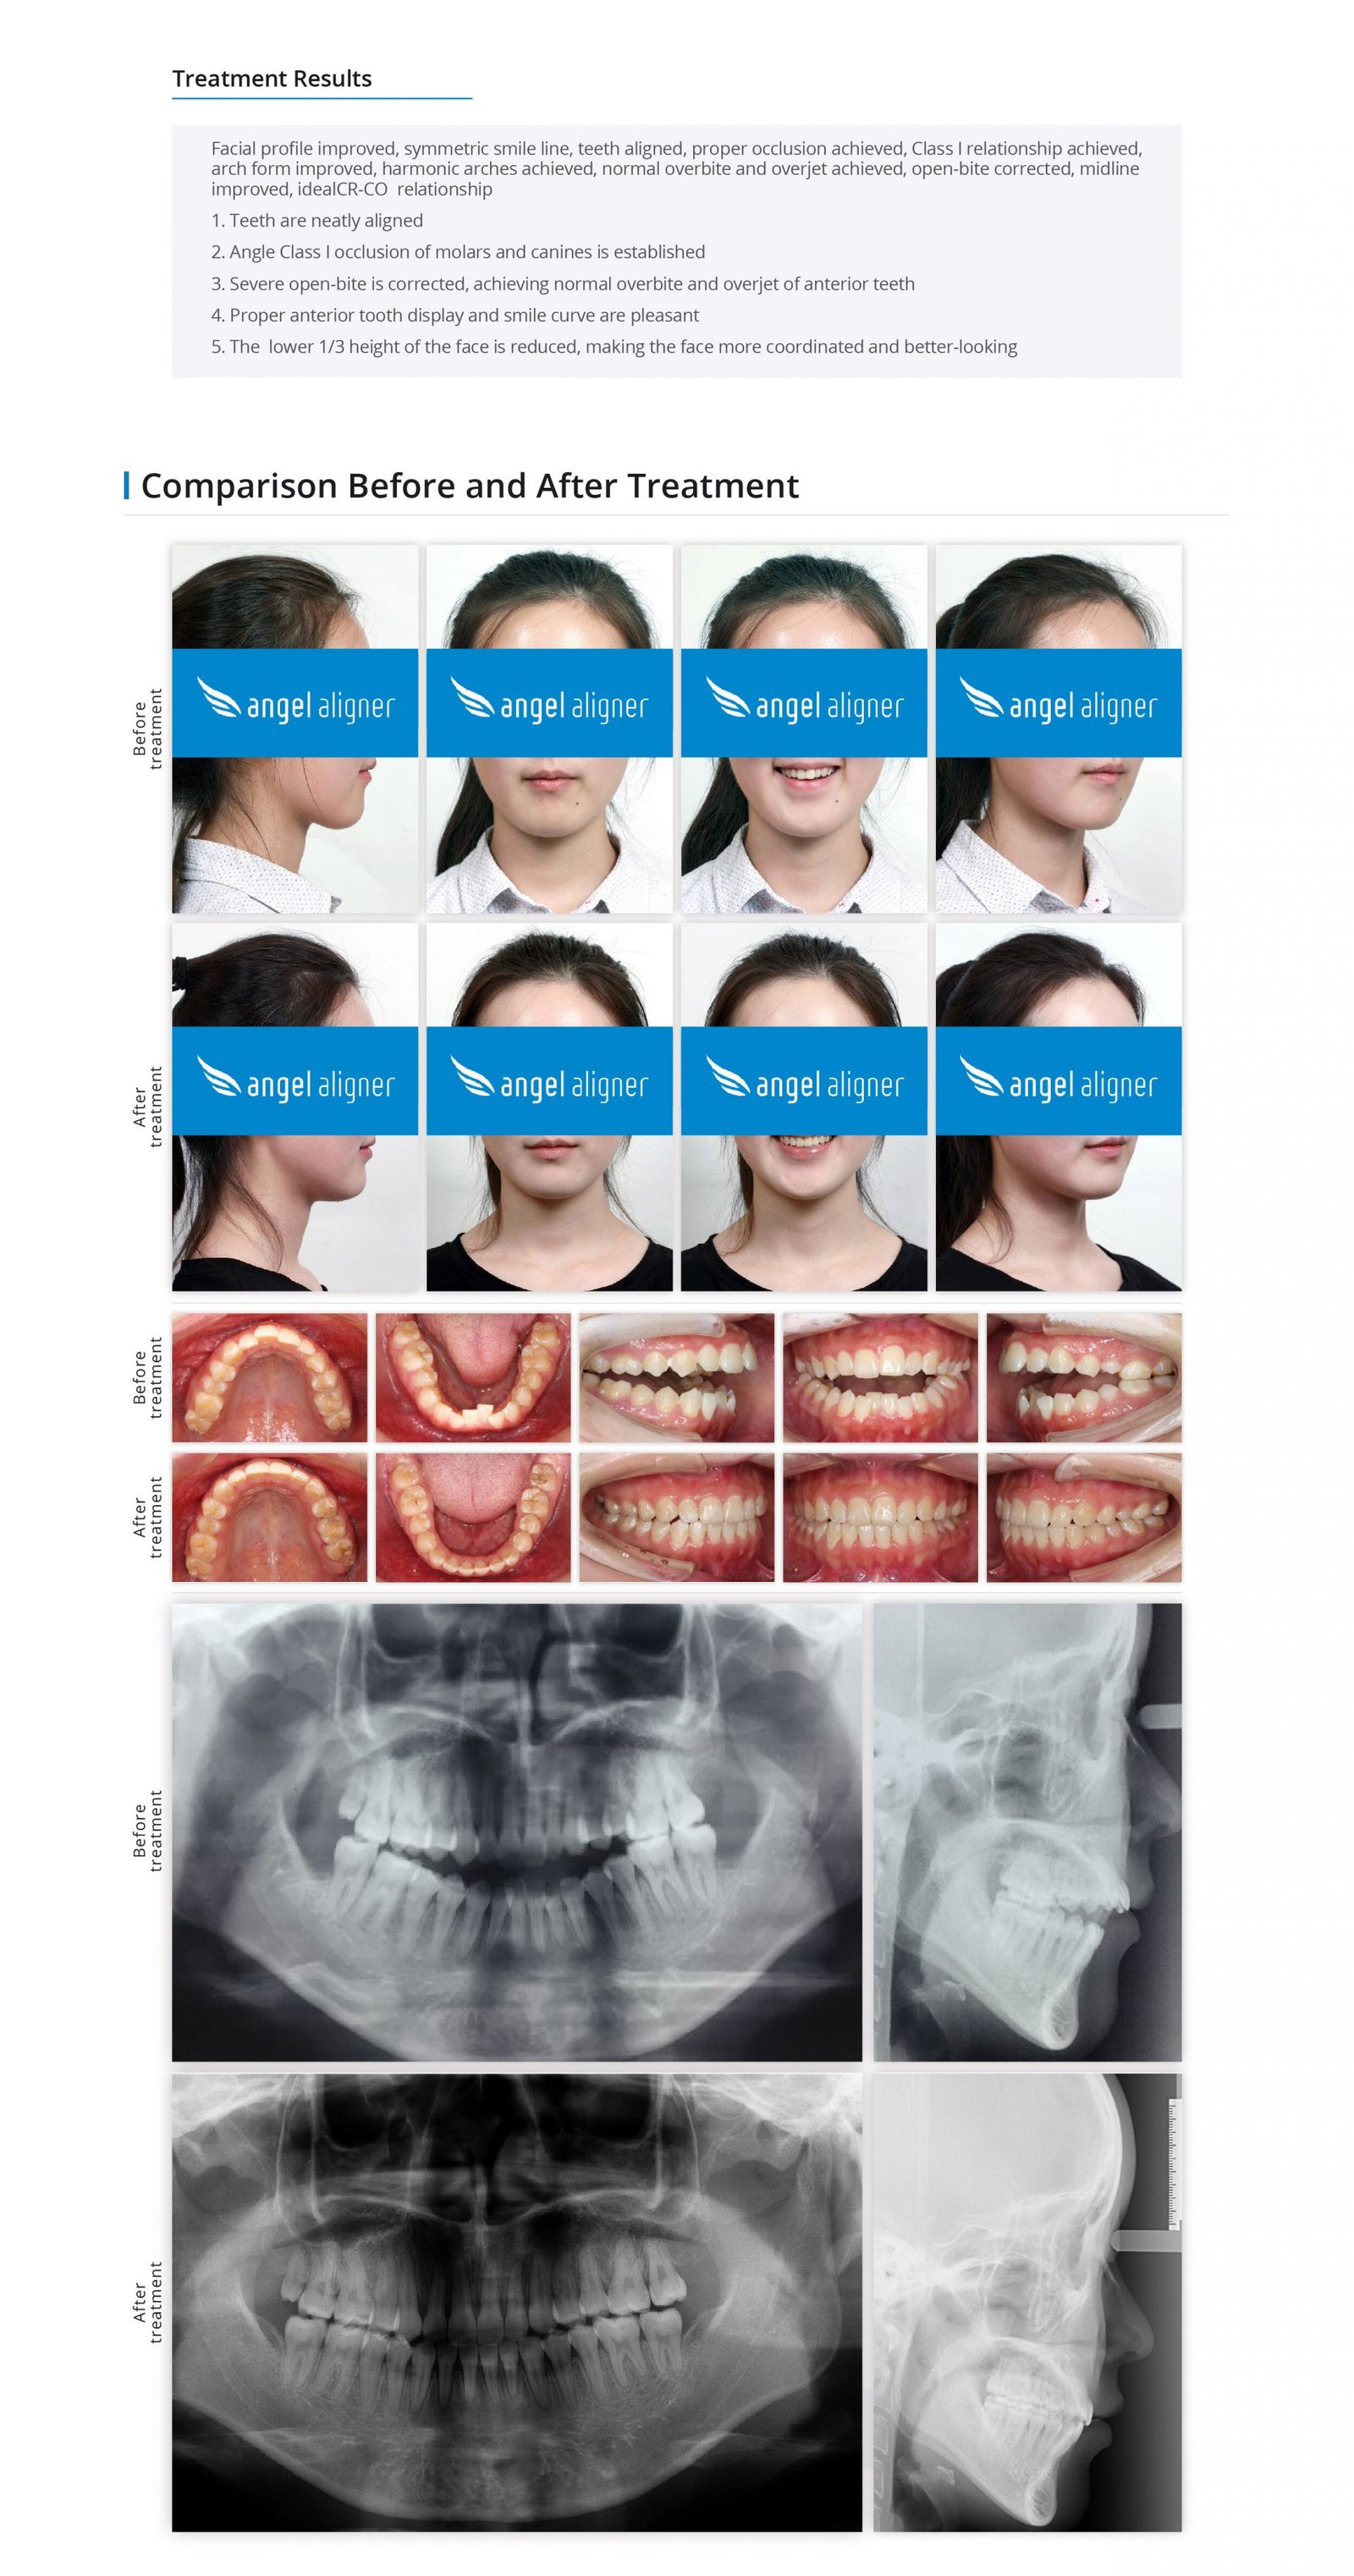

Treatment Of Anterior Tooth Severe Open-bite By Posterior Tooth Distalization And Intrusion With The Invisible Orthodontic Appliance

Patient Information

Female, 18 years old

Permanent dentition

Angel Aligner Pro

Total treatment time: 23 months